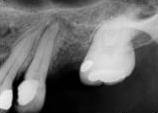

antes depois